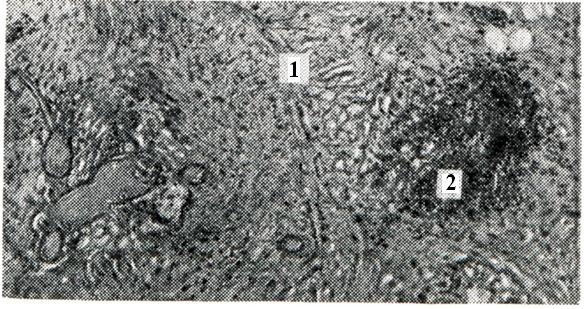

При гнойном воспалении суставов морфологически может быть: 1) гнойный синовит, или эмпиема; 2) флегмона капсулы; 3) гнойный панартртп. В начальных стадиях гнойного синовита экссудат может быть прозрачным, однако вскоре он становится гнойным или гнойно-геморрагическим. При наличии анаэробной и гнилостной флоры в нем могут образоваться пузырьки газа (гнилостный артрит). Микроскопически в синовиальной оболочке от- мечается лейкоцитарная инфильтрация, очаги некроза и развитие грануляционной ткани, наползающей в виде паннуса на суставной хрящ (рис. 4). В суставном хряще очень рано обнаруживаются участки дистрофии и некроза. В дальнейшем развивается некроз и секвестрация значительных участков хряща, а при травматических артритах — даже целиком всей костно-хрящевой пластинки. Хрящевые секвестры вначале образуются в зоне контакта с воспаленной синовиальной оболочкой и паннусом, что связывают с протеолитическим действием лейкоцитов и абсорбционными свойствами грануляционной ткани.

Рис. 4. | ||